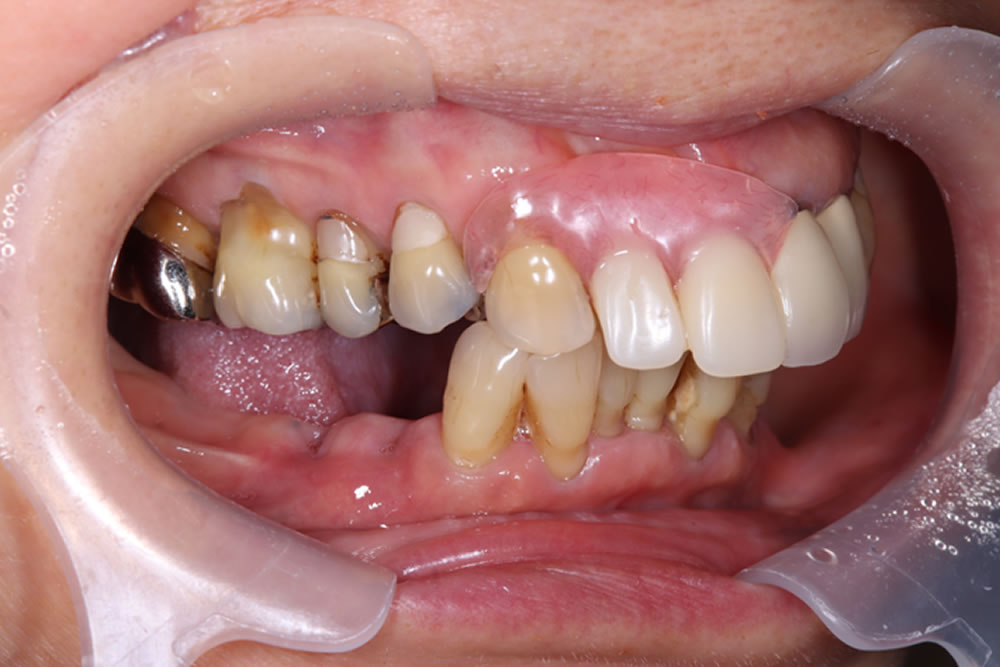

歯肉移植を併用したインプラント症例

こちらの患者さまは、右下奥欠損部へ歯を入れたいとの主訴で来院されました。来院1ヵ月前に他院にて右下奥歯を2本抜歯したとのことでした。

義歯やインプラントといった方法があり、メリットデメリットを説明したところ、今回はインプラントによる治療を希望されました。

また、口腔内全体の状態を確認すると、右上奥歯の挺出(下方に伸びている状態)も認めたため、上下でバランスをとって補綴する計画を立てました。

インプラント埋入手術の実施